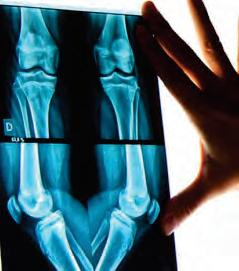

Carreón Ferreyra Ortopedia & Traumatología

Cédulas: 9708039 / 12070023

• Lesiones Deportivas

• Traumatología (Fracturas)

• Niños y adultos

• Artroscopia (rodilla y hombro)

• Pie: Hallux Valgus (juanete)

• Pie plano. Pie Cavo

Dr. José Ramsés Cruz Meléndez

Cédulas: 4318520 / 7361302

Alta especialidad en Cirugía de rodilla y cadera

• Fracturas y luxaciones

• Artroscopía

• Prótesis de rodilla y cadera

• Lesiones ligamentarias y tendinosas

• Patología de espalda

• Ortopedia pediátrica

FRACTURA DE CADERA

Las fracturas de cadera son lesiones comunes y graves, para las personas de la tercera edad, actualmente consideramos un gran aumento en la frecuencia que esta se presenta, debido a tres factores: mayor índice de sobrevida, en consecuencia, más osteoporosis, peor estado nutricional y accidentes de mayor energía. Estas fracturas pueden tratarse mediante diferentes técnicasquirúrgicas:

En resumen, tanto el clavo centromedular como la prótesis de cadera son opciones para el tratamiento de fracturas de cadera. La elección depende de la situaciónclínica,laedaddelpacienteylapreferencia del cirujano. Es fundamental evaluar cada caso individualmente para determinar la mejor opción terapéutica.

• Fracturas, Luxaciones, Esguinces

• Prótesis de Rodilla

• Trauma de Urgencia

• Artroscopia de Rodilla

• Reemplazo Articular de Cadera

• Cirugía de Pie y Tobillo